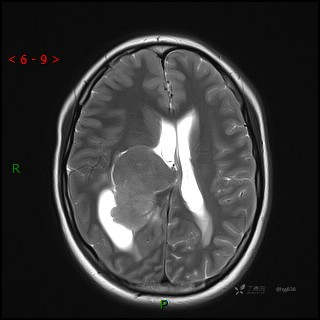

辅助检查:CT MRI

临床诊断:脑室占位

颅脑CT平扫

MRI平扫